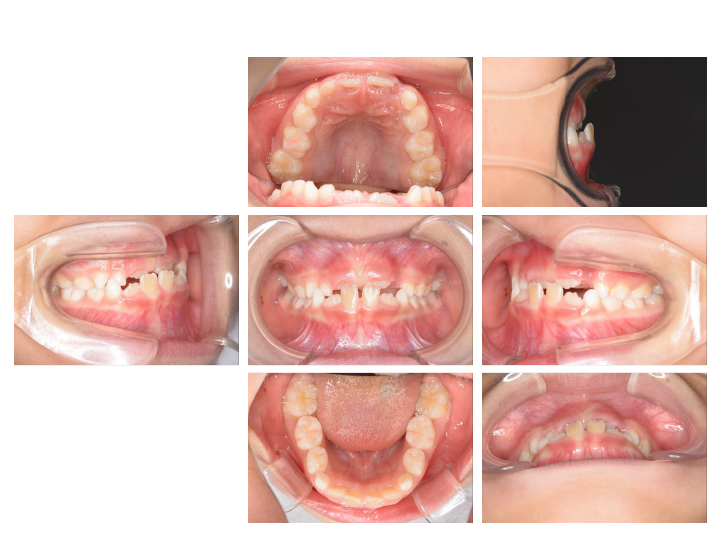

第1期治療

乳歯と永久歯が混じった時期の治療で、主に成長を利用した治療を行ないます。(6~10歳)